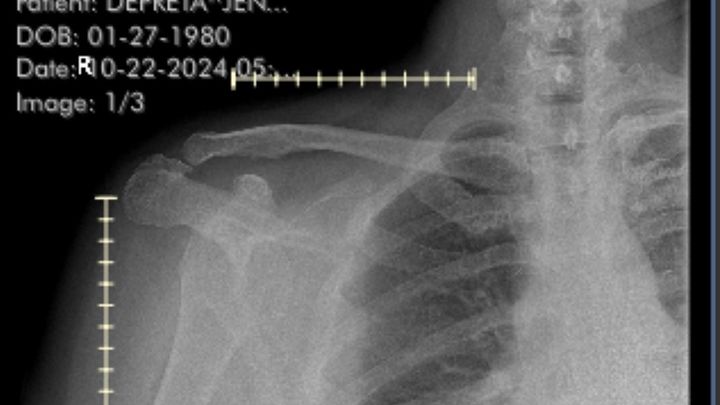

Jennifer is facing a challenging time as she navigates through the aftermath of a grand mal seizure that left her with bilateral dislocated shoulder and two broken humerus bones. As a mother of three Jennifer's ability to care for her family has been significantly impacted by this unforeseen medical emergency. This campaign has been launched to support Jennifer and her family during this difficult period. Any contribution, no matter how small, will make a difference in helping Jennifer get the medical treatment she needs and alleviating the financial burden that comes with such an unexpected health crisis. Your support and generosity will go a long way in assisting Jennifer on her road to recovery and ensuring that she can continue to be there for her children. Jennifer’s left shoulder, requires surgery further impacting her job as a hairstylist because of the length of recovery.